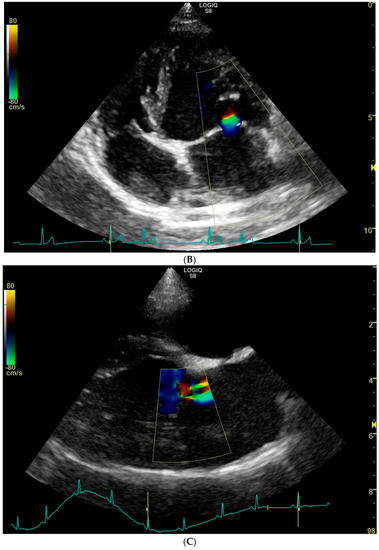

Trivial mitral valve regurgitation was detected in 26 dogs, resulting in a prevalence of 52%. No obvious morphologic changes were noticed on the mitral valve apparatus with 2D echocardiography. Mitral regurgitation appeared central in 24 dogs and eccentric in the remaining 2 dogs, of which in one case two small jets were noticed (Figure 1). Because of the small jet size, no attempts were made to measure the flow velocity of the regurgitant jet with spectral Doppler mode. Mitral valve regurgitation was equally prevalent in female dogs (19/36, 53%) compared to male dogs (7/14, 50%) (p = 0.86). Moreover, mitral valve regurgitation was equally prevalent in black and blonde dogs: 9/16 (56%) in the black and 17/34 (50%) in the blonde ones (p = 0.68).

Figure 1.

Color Doppler echocardiographic images (systolic frames) of trivial mitral valve regurgitation jets in three clinically healthy Labrador retrievers without heart murmur. (A). Standard right parasternal four-chamber view showing a central jet. (B). Standard left parasternal four-chamber view showing a central jet. (C). Standard right parasternal four-chamber view showing two eccentric jets.

Whether the trace mitral valve regurgitation is a physiologic finding, or a manifestation of a mild mitral valve dysplasia in the present study, remains unclear. However, because none of the dogs that underwent an echocardiogram from this dog breeding organization had more than trivial mitral valve regurgitation, mitral valve dysplasia as a possible cause of trace mitral valve regurgitation seems unlikely. As opposed to an assumed physiologic regurgitation, mitral valve dysplasia would likely manifest in various grades of mitral regurgitation. On the other hand, though presumed physiologic mitral valve regurgitations are thought to cause a central jet [5,18], we did identify dogs with an eccentric and more than one jet (Figure 1C).